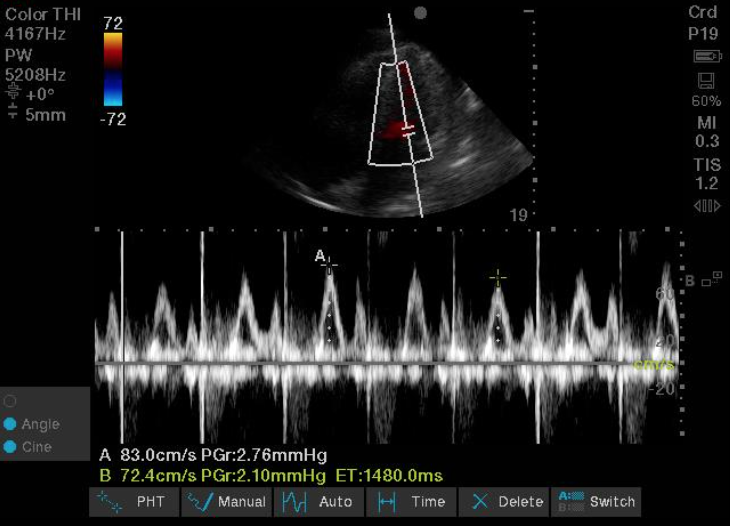

One of the most requested teaching topics I get from trainees on our medical wards is cirrhosis and liver disease 🩸

Here's part 1 (of several to come!) of my cirrhosis tips and tricks: a short 🧵